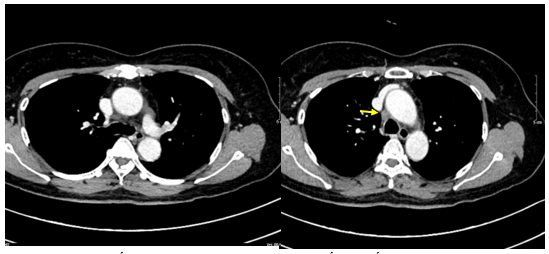

- Chụp cắt lớp vi tính lồng ngực: Nhu mô thùy trên phổi (Phải) có nốt tổn thương kích thước 13x14mm,bờ không đều, ngấm thuốc, sau tiêm. Rải rác nốt đặc 2 bên thùy phổi kích thước 3-10mm. Trung thất các nhóm 1R; 2R; 4R; 5; 8; 10RL có vài hạch lớn nhất kích thước 26x15mm; bờ không đều; ngấm thuốc không đồng nhất sau tiêm. Thượng đòn 2 bên có vài hạch tính chất tương tự; hạch bên phải kích thước 11x14mm

Hình 1.

Hình ảnh cắt lớp vi tính ngực có tiêm: thùy trên phổi (P) có nốt tổn thương kích thước 13x14mm, bờ không đều, ngấm thuốc, sau tiêm. Nghi ngờ tổn thương nguyên phát (mũi tên đỏ)

Hình 2: Hình ảnh cắt lớp vi tính ngực có tiêm: Rải rác nốt đặc 2 bên thùy phổi kích thước 3-10mm (các mũi tên màu xanh lá)

Hình 3: Hình ảnh cắt lớp vi tính ngực có tiêm: Trung thất các nhóm 1R; 2R; 4R; 5; 8; 10RL có vài hạch lớn nhất kích thước 26x15mm; bờ không đều; ngấm thuốc không đồng nhất sau tiêm (mũi tên màu cam)

Hình 6: Hình ảnh cắt lớp vi tính ngực có tiêm: đám xẹp đông đặc đỉnh phổi phải kích thước 11mm (mũi tên xanh nước biển)

Hình 7: Hình ảnh cắt lớp vi tính ngực có tiêm: Trung thất cân đối có vài hạch 10mm (mũi tên vàng). Hạch trung thất giảm kích thước rất nhiều chỉ sau 03 chu kỳ.

- Cắt lớp vi tính ổ bụng: Không phát hiện tổn thương bất thường.

Hình 10: Hình ảnh cắt lớp vi tính ngực có tiêm: Đám xẹp vùng đỉnh phổi phải, nốt đặc nhỏ kích thước 2-3mm

Hình 11: Hình ảnh cắt lớp vi tính ngực có tiêm: Không thấy hạch to hay khối trong trung thất

Nhận xét: Chỉ sau 03 chu kỳ Pemetrexed – Carboplatin – Pembrolizumab, hình ảnh chụp cắt lớp vi tính cho thấy tổn thương phổi nguyên phát và các hạch giảm kích thước đáng kể. Đáp ứng điều trị được đánh giá là đáp ứng một phần theo tiêu chuẩn RECIST 1.1. Sau 9 chu Pemetrexed – Pembrolizumab, bệnh nhân tiếp tục ghi nhận cải thiện rõ rệt các triệu chứng lâm sàng, thể trạng ổn định, không xuất hiện tác dụng không mong muốn nghiêm trọng.Đánh giá trên hình ảnh chụp cắt lớp vi tính cho thấy tổn thương phổi nguyên phát tiếp tục giảm kích thước không ngấm thuốc chỉ còn là đám xơ xẹp vùng đỉnh phổi phải, các hạch trung thất và ngoại vi thu nhỏ rõ rệt, không phát hiện được trên phim chụp và không ghi nhận tổn thương di căn mới.